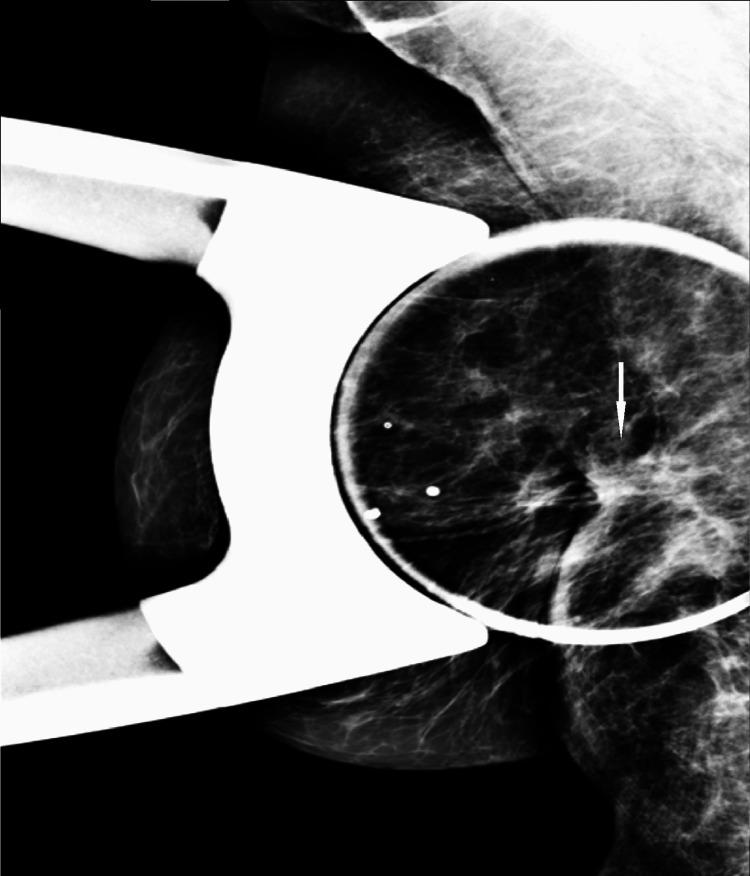

We describe a case of pathology-proven invasive lobular breast cancer (ILC) arising in a scar over 15 years after lumpectomy for previous invasive ductal carcinoma (IDC). The tumor was detected on screening mammography as a new focal asymmetry at the scar site and confirmed at diagnostic mammography. Ultrasound demonstrated an irregular, shadowing, hypoechoic mass at the scar site. Ultrasound-guided biopsy revealed poorly differentiated invasive lobular carcinoma. MRI and CT showed an irregular mass with pectoralis muscle invasion. Multimodality imaging findings are described. This is the first case to our knowledge reporting multimodality imaging findings of a breast cancer developing at the site of a surgical scar that is histologically different from the originally resected cancer.

我们描述了一例经病理证实的浸润性小叶乳腺癌(ILC)病例,该病例发生于先前因浸润性导管癌(IDC)行肿块切除术后15年以上的瘢痕处。肿瘤在筛查乳腺X线摄影中被检测为瘢痕部位新出现的局灶性不对称,并在诊断性乳腺X线摄影中得到证实。超声显示瘢痕部位有一个不规则、有阴影、低回声肿块。超声引导下活检显示为低分化浸润性小叶癌。MRI和CT显示有一个不规则肿块,侵犯胸大肌。描述了多模态成像结果。据我们所知,这是首例报告手术瘢痕部位发生的组织学上与最初切除的癌症不同的乳腺癌的多模态成像结果的病例。